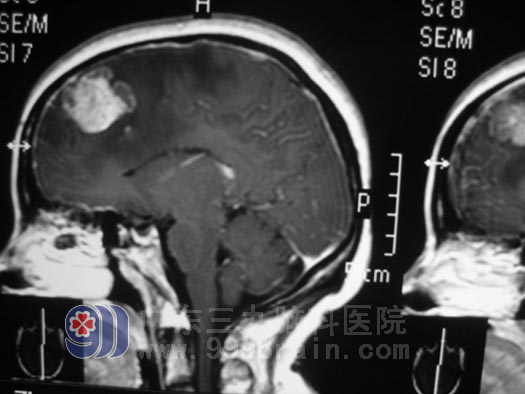

在广东三九脑科医院,神经外五科的鲁明主任为其做了详细的检查,头部MRI见双侧额叶、右侧丘脑占位!胸部CT见右侧肺部占位!腹部B超见肝右叶实质性占位!结合病史及影像学资料,钟阿姨全身多发性病变,考虑肺癌脑转移可能,左侧额叶病灶较大,水肿明显,压迫明显,病情紧急,在完善相关检查后立即安排了手术, 12月24日在全麻下行左侧额叶占位切除术,手术中见肿瘤质软,供血丰富,有出血及坏死,并见黄色囊液流出,肿瘤内侧紧贴大脑镰,在显微镜下对肿瘤进行全切,手术过程很顺利。第三天,钟阿姨已经可以下床活动了,术后病理结果为:转移性腺癌,免疫组化验检测结果提示癌组织源自肺。现在的她仍在行进一步的放射治疗中。

手术前